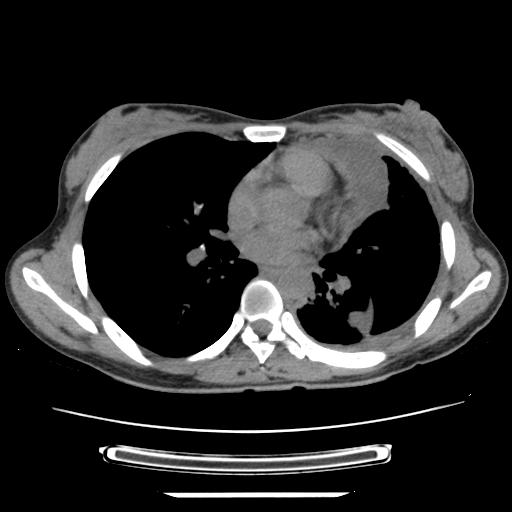

标题: CT21561:外院胸片提示胸腔积液,行CT检查。 [打印本页]

女,29岁,胸部不适,在外院胸片提示胸腔积液,到我院ct检查。

纵膈窗

左侧纵隔胸膜包裹性积液、左侧胸腔积液、胸膜肥厚粘莲,考虑结核性胸膜炎

左肺上叶不张,左侧胸水,叶间裂积液,纵隔淋巴结,脾脏钙化,考虑左肺上叶支气管内膜结核,结核性胸膜炎,脾结核

支持两肺继发性肺结核,左侧胸膜腔包裹性积液、胸膜肥厚,脾内多发钙化(结核钙化)。

左侧纵隔胸膜包裹性积液、左侧胸腔积液、胸膜肥厚粘莲,考虑结核性胸膜炎.左肺上叶支气管内膜结核,结核性胸膜炎,脾结核.

左肺上叶不张,左侧胸水,叶间裂积液,纵隔淋巴结,脾脏钙化,考虑左肺上叶支气管内膜结核,结核性胸膜炎,脾结核。支持!